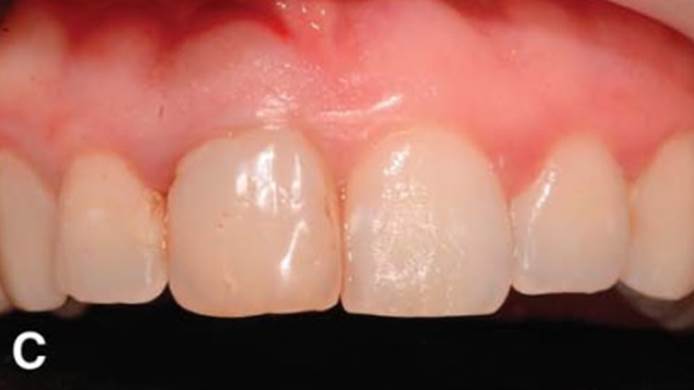

“AnyRidge with Root Membrane Technique shows

comparable long-term success rates to

conventional immediate implants. ”

Clinical case: Replacement of fractured central incisor (#11) with immediate implant

& Root Membrane Technique

- Courtesy of Dr. Miltiadis Mitsias, Greece -

Keywords

AnyRidge, Root Membrane Technique, retrospective study, long-term study, immediate implants, bone resorption, bone preservation, Dr. Miltiadis Mitsias,survival, success, maxillary anterior, single replacement

Products:

AnyRidge implant system, Root Membrane kit

Reference

The Root Membrane Technique: A retrospective clinical study with up to 10 years of follow-up./Implant Dent. 2018 Oct;27(5):564-574

https://www.ncbi.nlm.nih.gov/pubmed/30161062